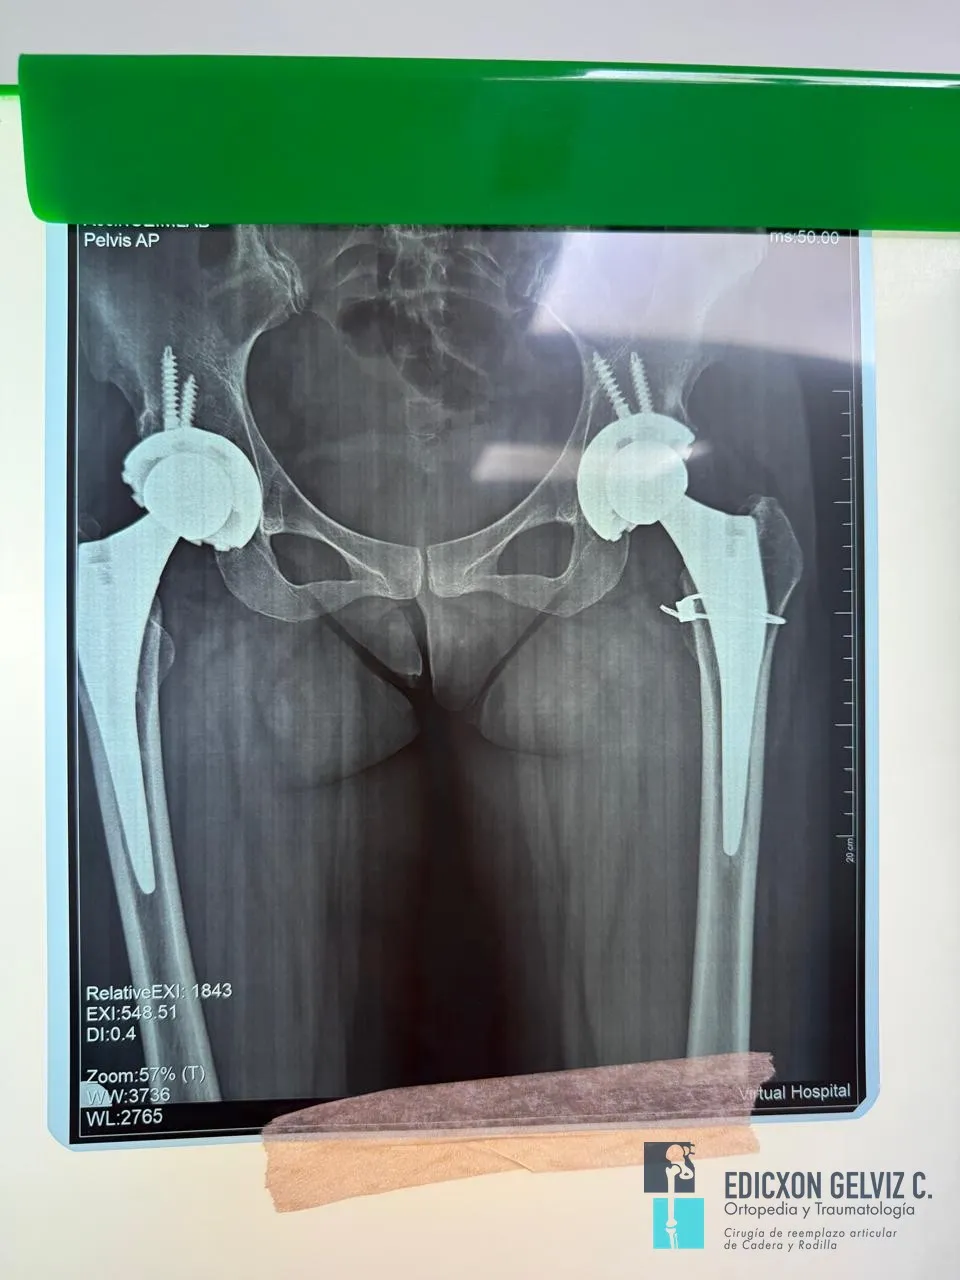

La radiografía postoperatoria confirma la correcta posición de ambas prótesis. Las incisiones se realizaron a través del pliegue inguinal, resultando en cicatrices mínimas y discretas.

Radiografía postoperatoria mostrando prótesis bilateral de cadera correctamente posicionadas

Radiografía postoperatoria: prótesis bilateral de cadera correctamente posicionadas.

Radiografía de seguimiento a 5 años con prótesis bilateral de cadera en buen estado

Radiografía de control a 5 años: prótesis bilaterales en excelente posición y sin signos de aflojamiento.